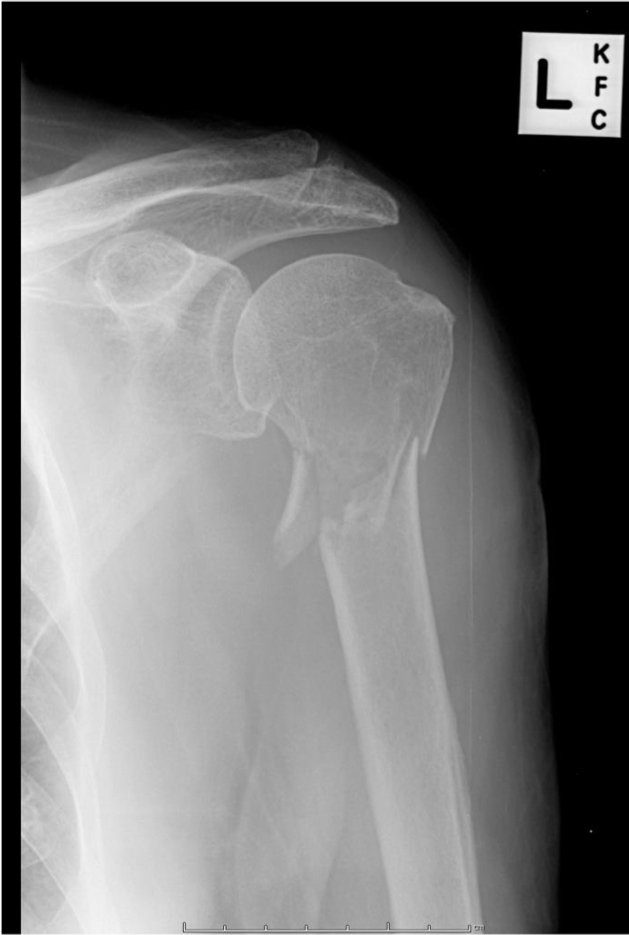

Clinical case: An 87 year old man fell at home. He had pain, deformity and bruising of his left arm. His X-ray is shown.

Which part of the humerus has been fractured?

What do you need to do in your examination of this patient?

During humeral shaft fractures that may affect the radial nerve, why is it better to test the motor function of the wrist than elbow?

As radial nerve comes down arm, the radial nerve has already given off some branches to triceps so will still get some extension at the elbow